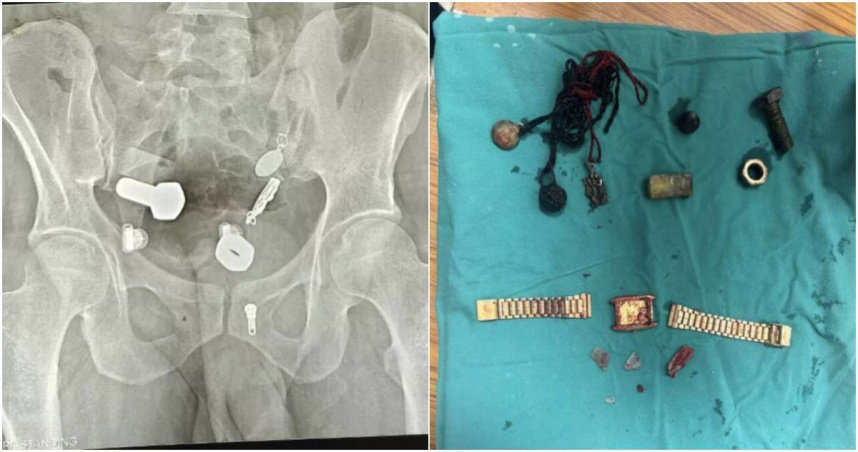

印度一名男子因嚴重腹痛到難以飲食而就醫,醫師本以為只是尋常的消化道問題,誰知在為他進行X光掃描時,意外在他體內發現了一系列匪夷所思的異物。(圖/翻攝Mirror)

近日,印度一名男子因嚴重腹痛到難以飲食而就醫,醫師本以為只是尋常的消化道問題,誰知在為他進行X光掃描時,意外在他體內發現了一系列匪夷所思的異物,包括一支手錶、螺母、螺栓及大量金屬碎片。院方最終為他進行了長達3小時的手術,才將所有異物成功取出。

據《Mirror》報導,這起案例發生在印度齋浦爾的沙瓦伊曼辛格醫院(Sawai Mansingh Hospital)。這名病患由家屬緊急送醫時,承受著劇烈的腹部疼痛,同時因無法進食飲水,身體十分虛弱。醫療團隊隨即替他進行X光掃描,卻赫然發現他的食道中卡著一支完整的手錶,而在他的大腸內,則積聚著大量鐵片、螺母、螺栓等金屬製品。這堆亂如五金行的雜物不僅數量驚人,且位置分散,嚴重威脅到病患的生命安全。

在別無選擇之下,醫療團隊在男子的腹部開了一個小切口,花了3個小時才小心翼翼地將所有異物逐一取出。幸運的是,在經過這場手術後,男子復原狀況堪稱良好。